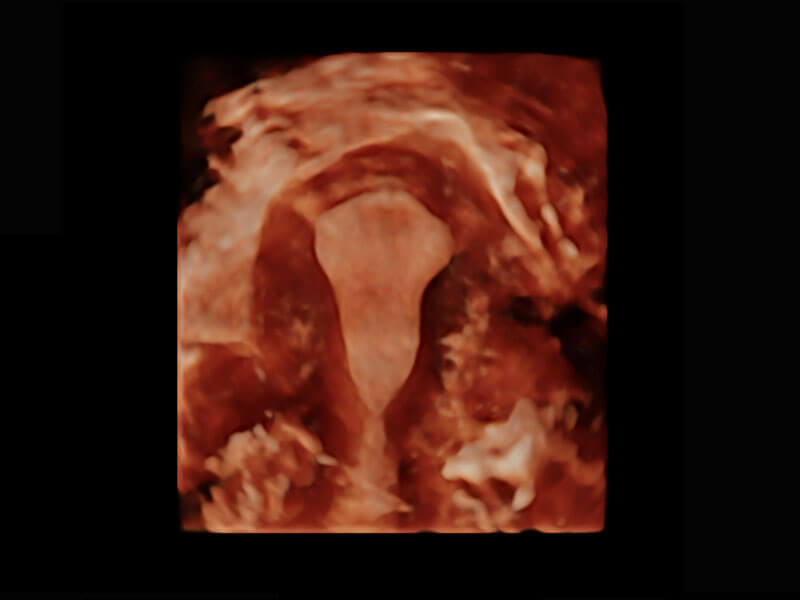

右室双出口

胎心容积成像